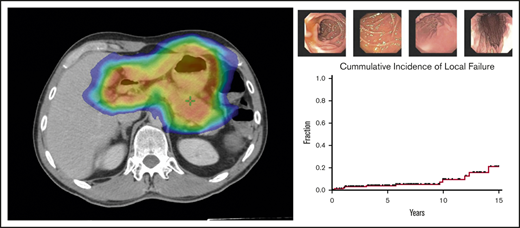

Treatment response to radiotherapy was assessed at 3 months by follow-up EGDs with multiple biopsies (Figure 2). Among the 166 patients who were treated for early-stage GML, posttreatment EGD with biopsy was performed in 160 patients, of whom 152 (95%) demonstrated a complete pathologic response (Wotherspoon 1-2) on the first posttreatment biopsy. Patients were serially followed by EGD biopsies in increasing intervals of 3 to 24 months.

EGD images documenting pathologic complete response. EGD images from patient 6, whose experienced spontaneous normalization without salvage treatment.

Over this extended follow-up period, 15 of 160 patients (9%) were found to have residual disease on EGD posttreatment biopsy (Wotherspoon 5; Figure 3). In addition, atypical lymphoid cells, not diagnostic of lymphoma (Wotherspoon 3-4), were described in 15 of 160 patients (9%). Six of the 15 patients (40%) with residual lymphoid cells subsequently progressed to local failure. Three of 20 patients (15%) with posttreatment residual disease experienced spontaneous resolution of their pathologic abnormalities on subsequent biopsy and, thus, were considered free of disease. The median interval from last radiation treatment to spontaneously resolved biopsy was 9 months (range, 8 months-3 years).

Natural history of EGD abnormalities. Fifteen patients who presented with early-stage GML exhibited residual GML on posttreatment EGD biopsy. Pathology review reported no evidence of disease (green circle), atypical lymphoid cells (blue circle), or residual GML (red open circle). Five patients with atypical lymphoid cells subsequently progressed to local failure (patients 2, 3, 4, 5, and 9). Three patients (6, 8, and 14) had pathologic EGD failures that self-resolved with observation alone.

Local failures

Over a median follow-up of 6.2 years from the end of RT (range, 19.7 months-23 years), 12 of 166 patients (7%) treated for early-stage disease experienced local failures. Five-year and 10-year local failure rates, using death as a competing risk, were 3.9% and 8.3%, respectively (Figure 4). Median time to local disease failure was 4.4 years (range, 3 months-14 years). One patient who developed DLBCL of the stomach 1 year after RT was treated with cyclophosphamide, doxorubicin, vincristine, and prednisone (CHOP) chemotherapy and died of disease a year later. The remaining local relapses were associated with refractory GML on EGD biopsy. Salvage therapies included rituximab, additional radiotherapy, and rituximab (R)-CHOP.

Local and distant disease failures. Cumulative incidence of local and distant failures for patients treated for early-stage GML (N = 166), using death as a competing risk. Five-year and 10-year local failure rates were 3.9% and 8.3%, respectively, whereas 5-year and 10-year distant failure rates were 6.9% and 11%, respectively.